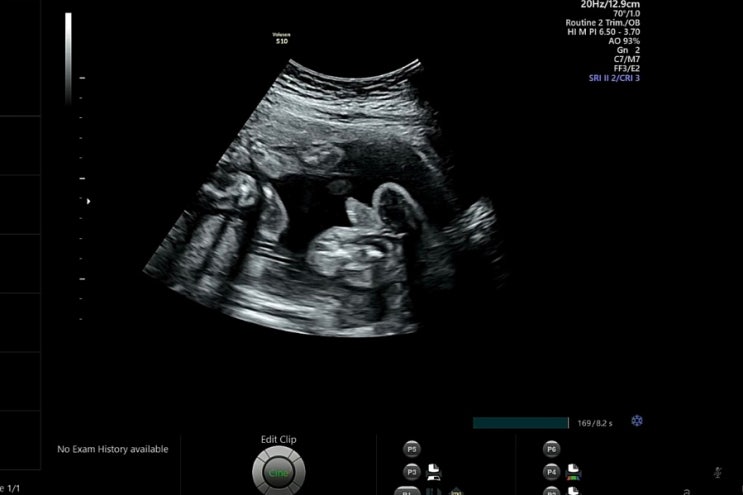

2023. 08. 09 (수) 당진 미즈맘으로 전원 후 딱 17주가 되는 날인 8월 9일! 2차 기형아 검사를 위해서 방문...